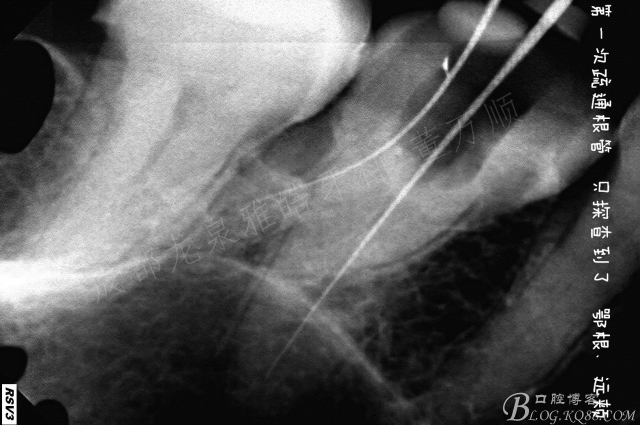

10多年前的治疗,最担心的就是塑化治疗。

根管影像模糊不清 看到这种片子 我心里是没底的

第一次简单去除原充填物 疏通了一下根管 鄂根还是非常顺利的下去了,远中只能下去一点点,近中没有发现根管口迹象。

复诊的时候 着重去寻找近颊根,配合超声,此时一定要有耐心,慢慢的8号挫有感觉了

照插针片的时候 感觉远颊下去的时候 瞬间有落空感,伴有轻微疼痛

一看牙片,坏了,肯定是侧穿了,心情平和一下,封药,改约时间下次预备

按时复诊 ,过程你懂的 8号挫预弯,找啄歰感 配合牙片,1次 2次 3次......

经过半个小时努力总算是找到了 预备,荡洗 根充。

术后症状消失了 远颊还是没有做的很理想 只能观察 ,患者左侧做的种植修复 ,可以长期跟踪预后。期待有个好结果。